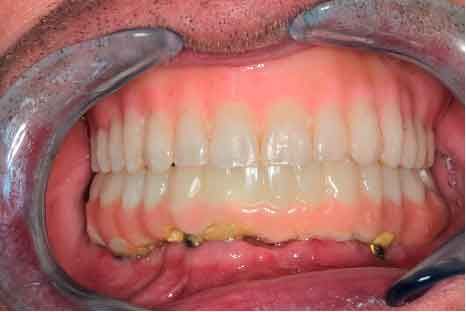

66 years old patient. Wishes to regain functional comfort and improve aesthetics.

Complaints :

- Lack of stability of his removable prosthetics

- Difficulties in eating

- Sagging of the upper lip

The periodontal structures of the remaining teeth are no longer sufficient. An edentulism is considered. The treatment plan is directed towards a removable maxillary complete prosthesis and an implant-supported mandibular complete prosthesis.

Picture - Initial bite situation